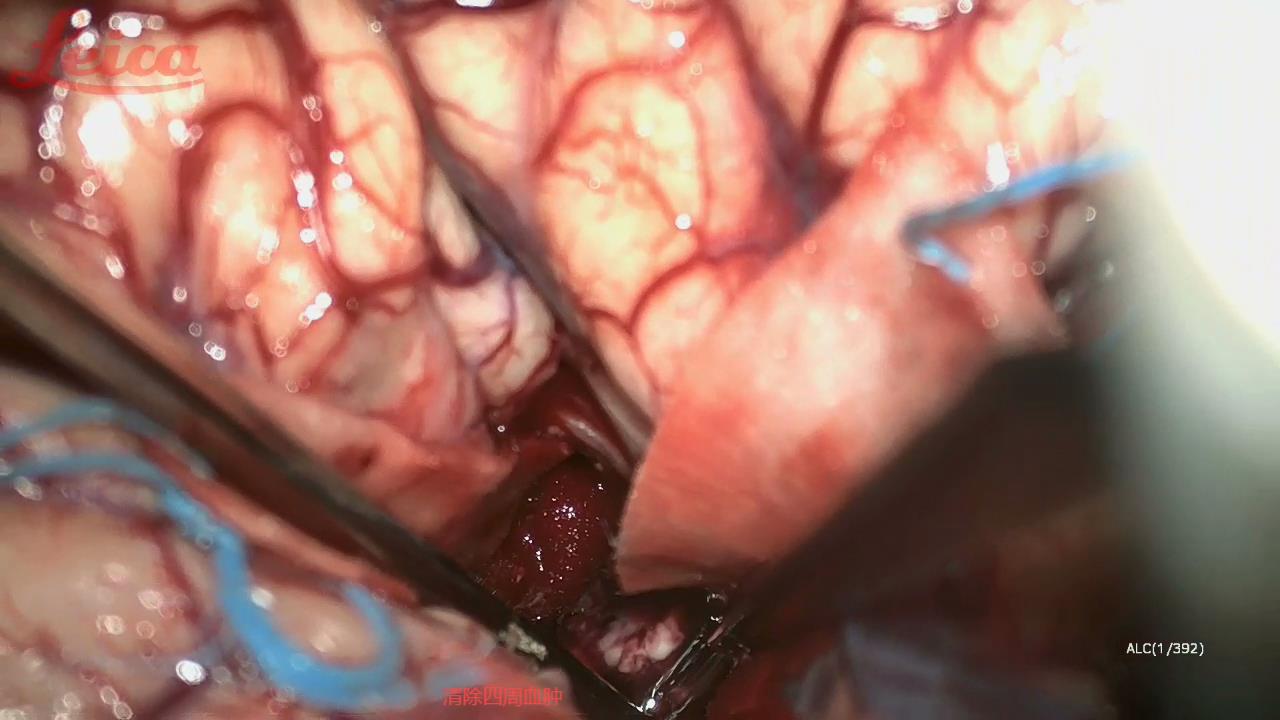

经外侧裂-岛叶造瘘清除血肿简要

经外侧裂-岛叶造瘘清除基底节出血